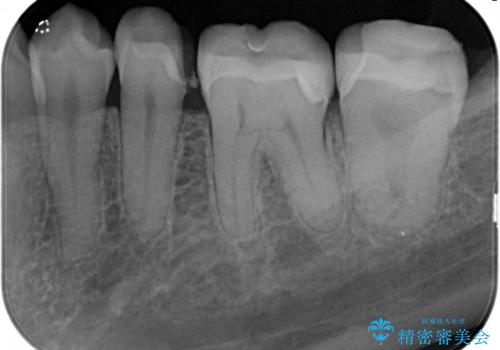

虫歯の治療(セラミックインレー)

- 定期検診にて虫歯が見つかり、セラミックインレーに治療を行っております。

e-max プレスインレーにて修復治療を行っているため適合性及び審美性の高い治療を行うことができます